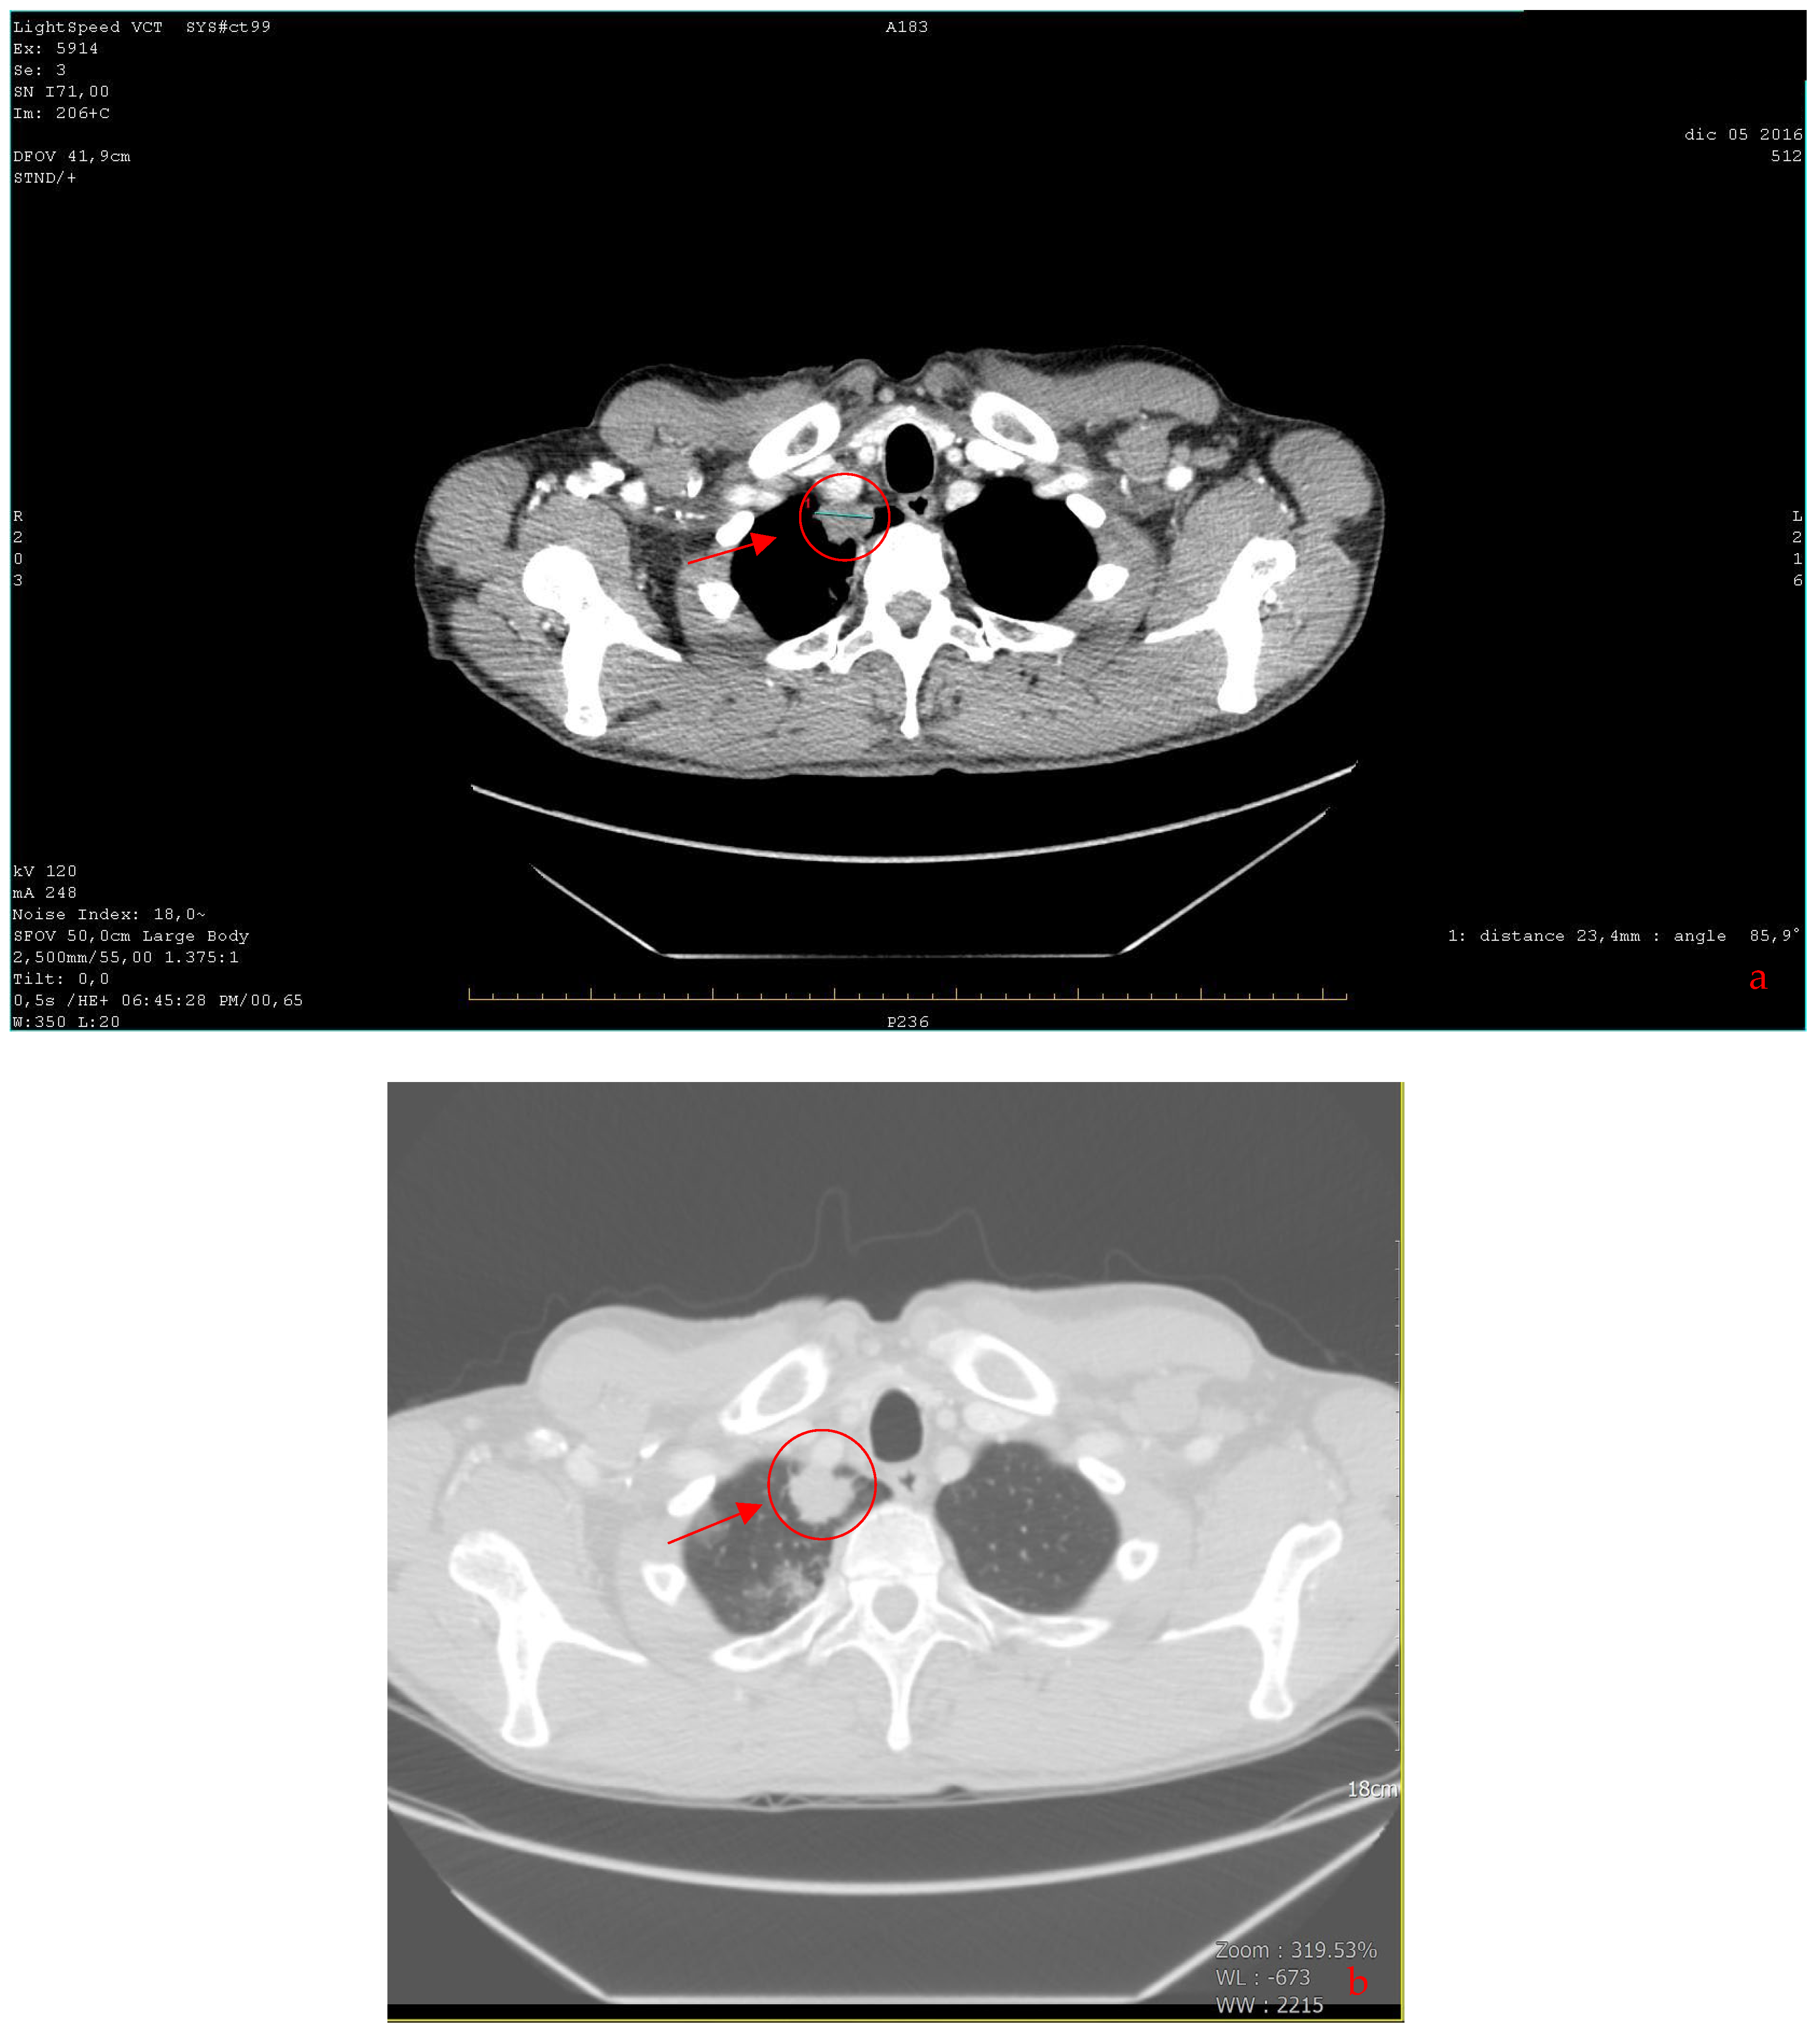

| 2016 | Patient presentation Diagnosis Abdominal ultrasound Total body CT scan | Worsening non-productive night cough, no dyspnea. Metastatic lung cancer. Presence of malignant lymph nodes near the hepatic hilum. Solid nodular- like expansive process in the right upper lobe of the lung and multiple lymphadenopathies in the mediastinum and abdomen. |